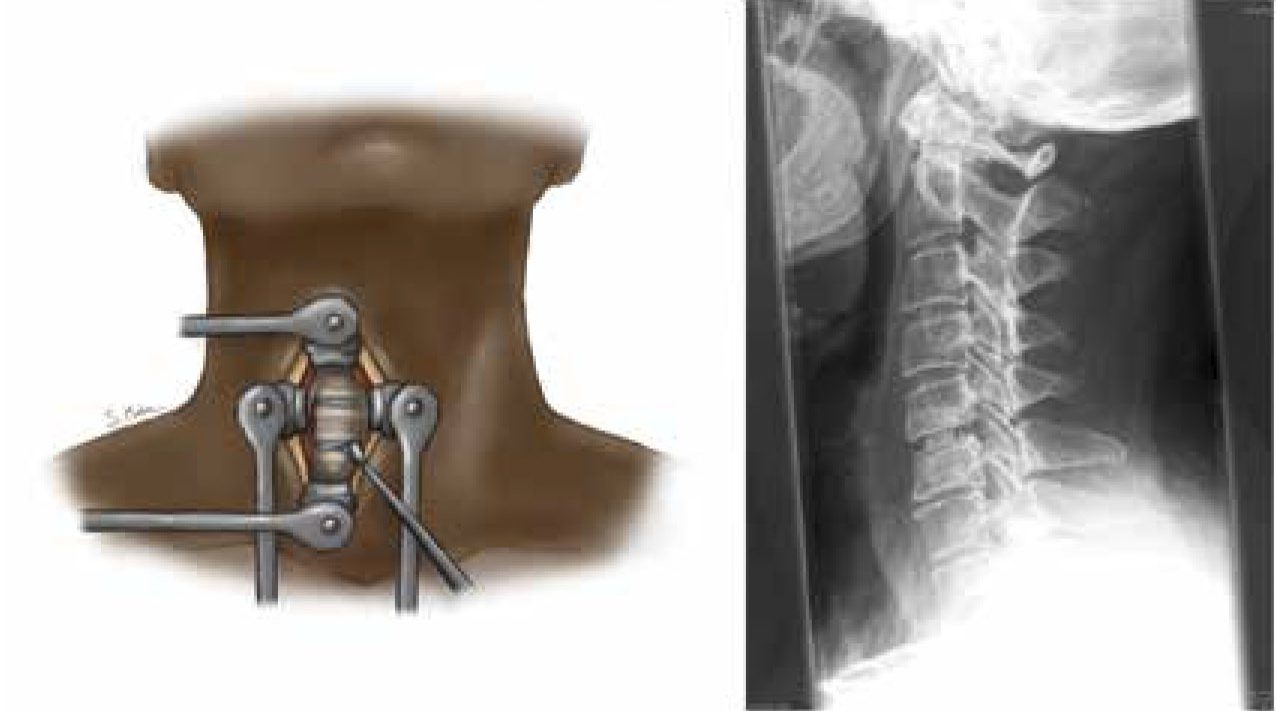

Klinik och vetenskap Grundläggande neurologisk undersökning viktig för att skilja mellan tillstånden